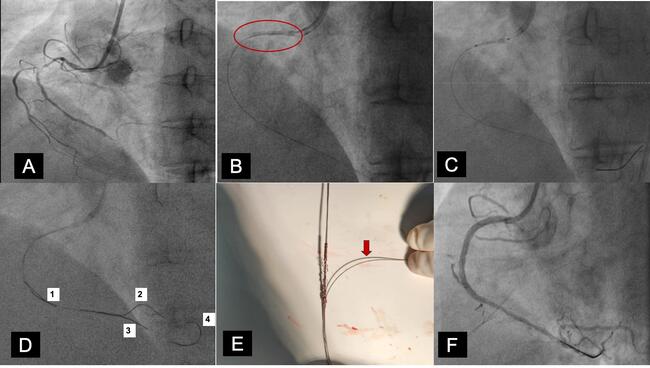

Figure. (A) Coronary angiogram in left anterior oblique view showing diffuse lesion causing 90% stenosis in the mid-right coronary artery (RCA), followed by distal cut off. (B) Fluoroscopy image showing dislodged coronary stent in the proximal portion of RCA (circle) just distal to the guiding catheter. (C) A 2 x 10-mm balloon failed to cross the stent due to crumpling of the dislodged stent because of the guide-induced trauma. (D) Multiple wires were passed distal to the stent (indicated by numbers). (E) Photograph showing the retrieved stent; 3 wires have passed through the lumen of the stent and fourth wire (arrow) has passed through the struts of the stent. (F) Final angiographic result after successful stent deployment.